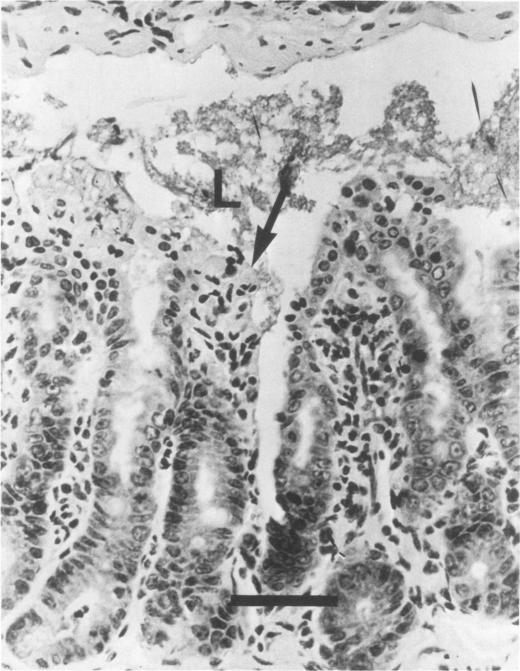

Hamster (Mesocricetus auratus) enteritis caused by epithelial cell-invasive Escherichia coli.

When inoculated orally, Escherichia coli strain 1056 caused acute enteritis in 7 of 22 weanling hamsters. E. coli strain 1056 was isolated from the ileum of a hamster with proliferative ileitis. It was lactose negative, nonmotile, and anaerogenic. By electron microscopy and indirect fluorescent-antibody techniques, E. coli strain 1056 was detected in absorptive epithelial cells, resembling invasive E. coli and shigella infections of other species. Ileitis did not progress to epithelial cell hyperplasia, which is characteristic of proliferative ileitis of hamsters. A control group of 10 hamsters, inoculated with nonenteropathogenic E. coli isolated from a normal hamster, did not develop signs or lesions.